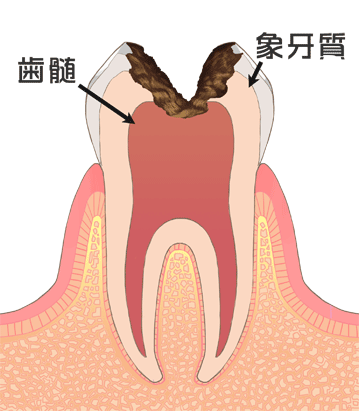

⑥ 前回詰めた綿花の状態を確認して、良い状態なら、「根管充填剤」(マスターポイント・アクセサリーポイント)というお薬を、余分な空間がないように根っこに詰めます。

⑥ 前回詰めた綿花の状態を確認して、良い状態なら、「根管充填剤」(マスターポイント・アクセサリーポイント)というお薬を、余分な空間がないように根っこに詰めます。 Q1.痛みはありますか?

Q1.痛みはありますか? ② 次に、「根管長測定器」という機械を使い、根っこの長さを正確に測ります。

② 次に、「根管長測定器」という機械を使い、根っこの長さを正確に測ります。

⑤ 次に、仮詰めをします。

⑤ 次に、仮詰めをします。 虫歯が神経まで達して炎症を起こしているので、人によってはズキズキとした痛みを感じる方もいます(>_<)

虫歯が神経まで達して炎症を起こしているので、人によってはズキズキとした痛みを感じる方もいます(>_<)